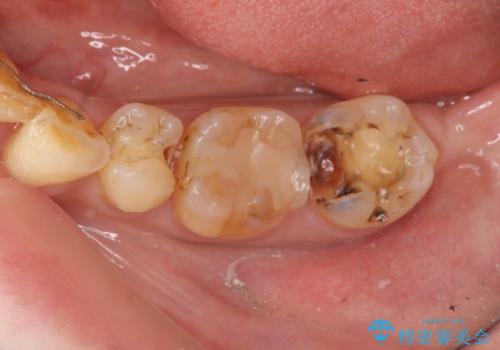

銀歯の下で虫歯の再発 拡大鏡下で行う虫歯の精密治療

- 他院で銀歯の下部に再発した虫歯の存在を指摘され、精密な治療を求めて来院されました。

銀歯下に虫歯が再発すると神経に近くなり、根管治療を必要とする可能性が高まってしまいます。

健全な歯を削らないように拡大鏡下で丁寧に虫歯を除去することで神経を温存し精密なセラミック治療を行うことができました。